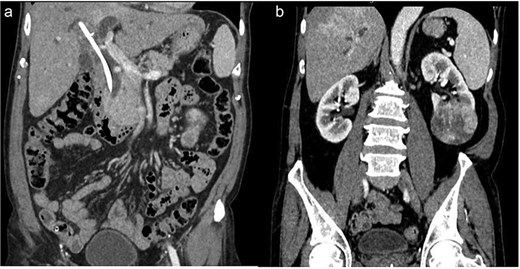

After multidisciplinary tumour board discussion, the patient planned for left radical nephrectomy and open CBD exploration through midline approach because of left RCC. The per op findings were grossly enlarged left kidney with surface protuberance present at lower pole (Fig. 2b), dense adhesions were present at right subhepatic region and grossly dilated mid & distal CBD stony hard in consistency (Fig. 2a) filled with multiple calculi (largest 3 × 2 cm), previously inserted CBD stent present. The patient underwent left radical nephrectomy along with choledocho-duodenostomy in a single sitting. The retained stent and sludge were removed successfully. The patient recovered uneventfully and was discharged on post op day 7. Histopathology confirmed chromophobe cell RCC, Fuhrman grade I (pT2aN0M0) and immunohistochemistry showed CD10 and CD117 positive along with CK7 negative. At 3-month follow-up, the patient remained asymptomatic.

(a) Dialated CBD. (b) Formalin fixed specimen of left kidney showing mass at lower pole.